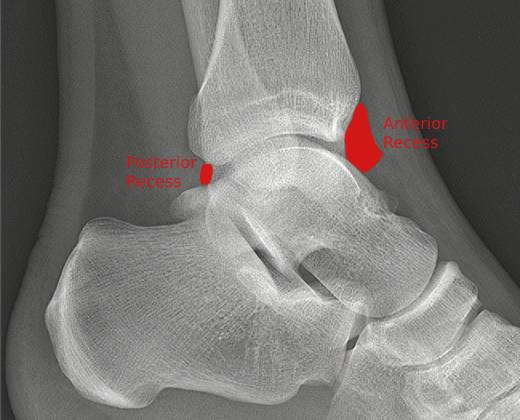

An ankle joint effusion is only appreciable on the lateral projection. The ligaments around the ankle joint (the big deltoid ligament medially and the talofibular/calcaneofibular ligaments laterally) restrict expansion of the joint capsule to the anterior and posterior recesses, small spaces enclosed by surrounding anatomy, shown very approximately below.

When the joint capsule is expanded by the effusion, the adjacent fat planes are displaced and we see the now familiar, slightly radiopaque culprits. Filling of the posterior recess is poorly appreciated on radiographs due to overlying bony anatomy, therefore looking within the anterior recess for what is known as the “teardrop sign”, a grossly ovoid opacity obscuring or distorting the anterior fat pad, is what will give us our diagnosis of ankle joint effusion.